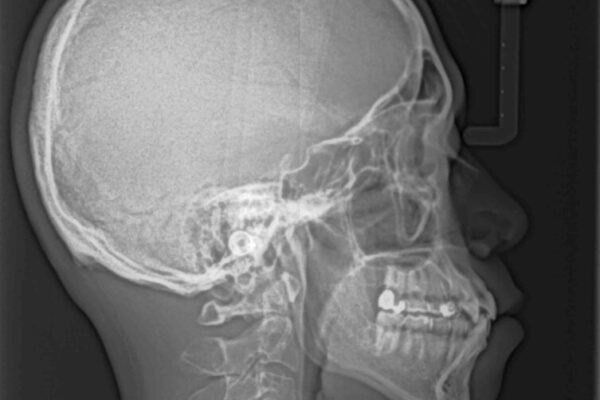

「八重歯を治したい」とご相談いただいた患者様の症例をご紹介します。

上下の前歯部に強い叢生(ガタガタの歯並び)があり、そのまま歯を並べると出っ歯になってしまう可能性がありました。

そこで、上下左右の第一小臼歯を抜歯し、歯が並ぶためのスペースを確保し叢生を解消する治療計画を立てました。

治療前

• 八重歯と前歯のガタガタを抜歯矯正で治療|クリアブラケット使用例 治療前画像